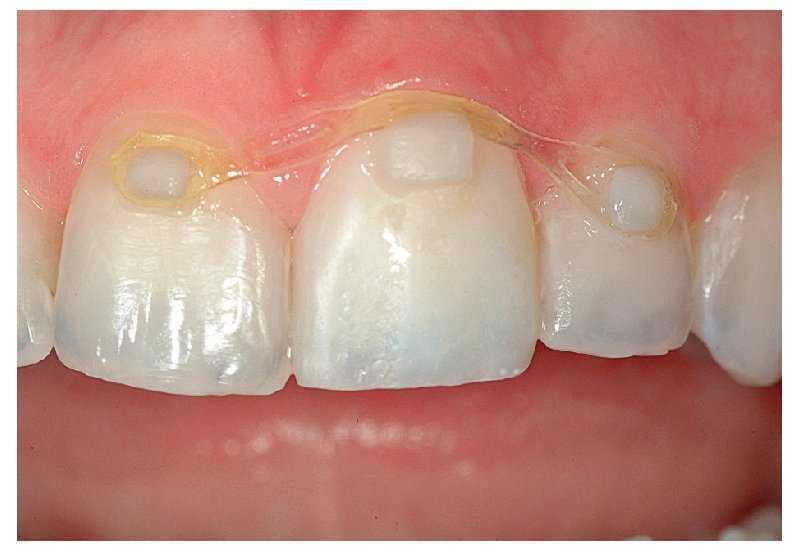

Una mujer de 21 años se mostraba insatisfecha con el entorno periodontal y el color de su corona en el diente 21, que le había sido colocada apenas un año antes tras un accidente. La anamnesis arrojó resultados normales. Durante el examen clínico, el color de la corona se reveló insatisfactorio. La encía estaba irritada y presentaba una recesión; el margen discurría 2 mm más hacia apical que en el diente 11 adyacente (fig. 3a). La corona estaba ligeramente sobrecontorneada en el margen. No pudo esclarecerse si la recesión gingival -el principal problema desde el punto de vista clínico- era atribuible al ajuste deficiente de la corona, al trauma original o a una combinación de ambos.

Fig. 3a. Vista desde frontal. La corona había sido colocada menos de un año antes del tratamiento aquí descrito.

Después de retirar la corona, durante el examen de la preparación del diente se reveló que ésta era ligeramente insuficiente, ya que la forma y la configuración marginal no eran aceptables (figs. 3b y 3c). En consecuencia se procedió a una nueva preparación del diente y se confeccionó una corona provisional. Tras la colocación de la corona provisional fue posible reevaluar la reacción tisular, que en este caso revestía una importancia prioritaria. También se estudiaron los contornos y el color del diente, a fin de determinar el procedimiento ideal a seguir (figs. 3d y 3e). Para la optimización del resultado del tratamiento fue necesario un tratamiento ortodóncico sencillo y poco laborioso. La paciente se declaró conforme con la planificación del tratamiento (fig. 3f). El objetivo era mejorar, mediante extrusión del diente, la proporción entre la longitud y la anchura de la corona en la corona provisional y en la posterior corona definitiva. En este proceso se alteraría la altura de la encía, al acompañar el hueso y el tejido periodontal el movimiento del diente24,32,55. Para ello se redujeron la superficie lingual y el borde incisal de la corona provisional, de modo que pudiera tener lugar la extrusión sin traumatización oclusal secundaria (fig. 3g).